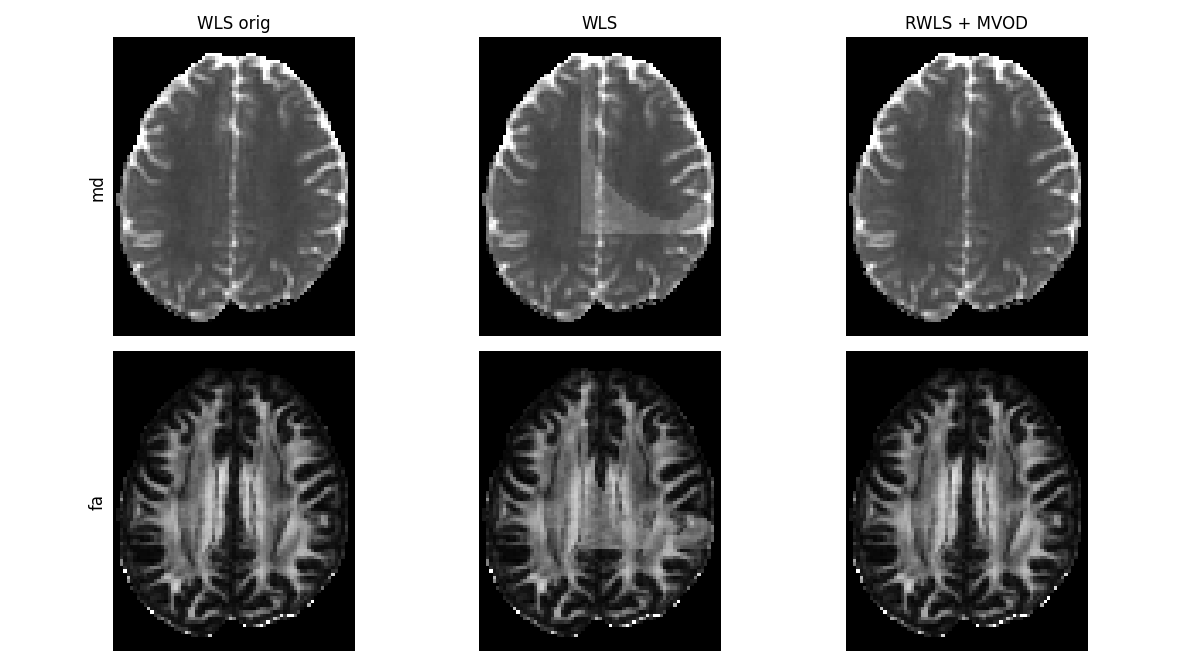

Robustly fitting (via IRLS) with the new weights function gives much better results.

compare_maps(

[tenfit_orig, tenfit, tenfit_rwls_mvod],

["md", "fa"],

fit_labels=["WLS orig", "WLS", "RWLS + MVOD"],

map_kwargs=[{"vmin": 0.000, "vmax": 0.002}, {"vmin": 0, "vmax": 1.0}],

filename="Compare_WLS_and_RWLS_MVOD.png",

)

WLS and RWLS with MVOD on the corrupted data, compared to the original fit.